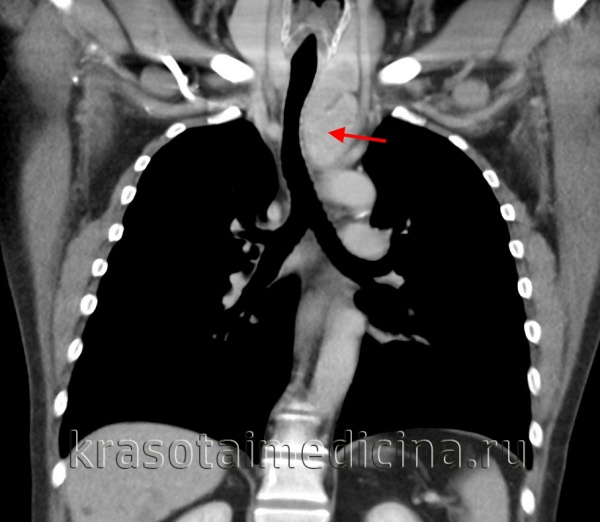

При полипозиционной рентгенографии грудной клетки в типичных случаях определяется шаровидная или овальная гомогенная тень средней интенсивности, с четкими контурами. При наложении тени средостения на тень кисты дополнительно требуется проведение пневмомедиастинографии или рентгенографии пищевода с бариевой взвесью. Установить анатомические взаимоотношения бронхогенной кисты с трахеобронхиальным деревом позволяет бронхоскопия и бронхография. При наличии признаков сдавления верхней полой вены или грудного лимфатического протока целесообразно выполнение флебографии и лимфографии.

Отличительным признаком тонкостенных бронхогенных кист служит изменение их конфигурации и положения при введении газа в средостение или плевральную полость (в отличие от дермоидных кист с толстой стенкой или плотных опухолей средостения). МСКТ грудной клетки в ряде случаев позволяет отказаться от проведения инвазивной диагностики бронхогенных кист и заранее спланировать объем вмешательства, поскольку дает исчерпывающую информацию о локализации и размерах образования.

- Рентгенологические исследования. Полипозиционная рентгеноскопия и рентгенография грудной клетки, рентгенография пищевода и сердца, пневмомедиастинография позволяют определить локализацию, форму и размеры кисты, ее связь с соседними органами, изменение положения при дыхательных движениях.

- Томографическая диагностика. Для более детальной оценки структуры, толщины стенок кисты, характера содержимого и взаимоотношения с соседними анатомическими образованиями, производится КТ и МРТ средостения.